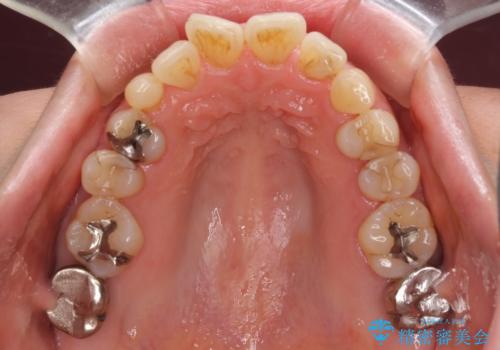

口元の出っ張りとデコボコを改善したい

- 近医にてインプラント治療を行った後に矯正治療を希望され、来院された患者様です。

口元の突出感とデコボコが気になっているとのことでしたが、インプラントが既に3本埋入されていたため、抜歯矯正による口元を引っ込めることができない状況でした。

近医での歯周病治療の影響でブラックトライアングルが発現していたため、IPR(歯と歯の間を削る)で隙間を改善しつつ、インプラントを固定源に歯列全体を後方へ移動させることとしました。